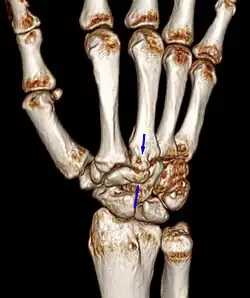

Additional images

Carpal boss in CT.